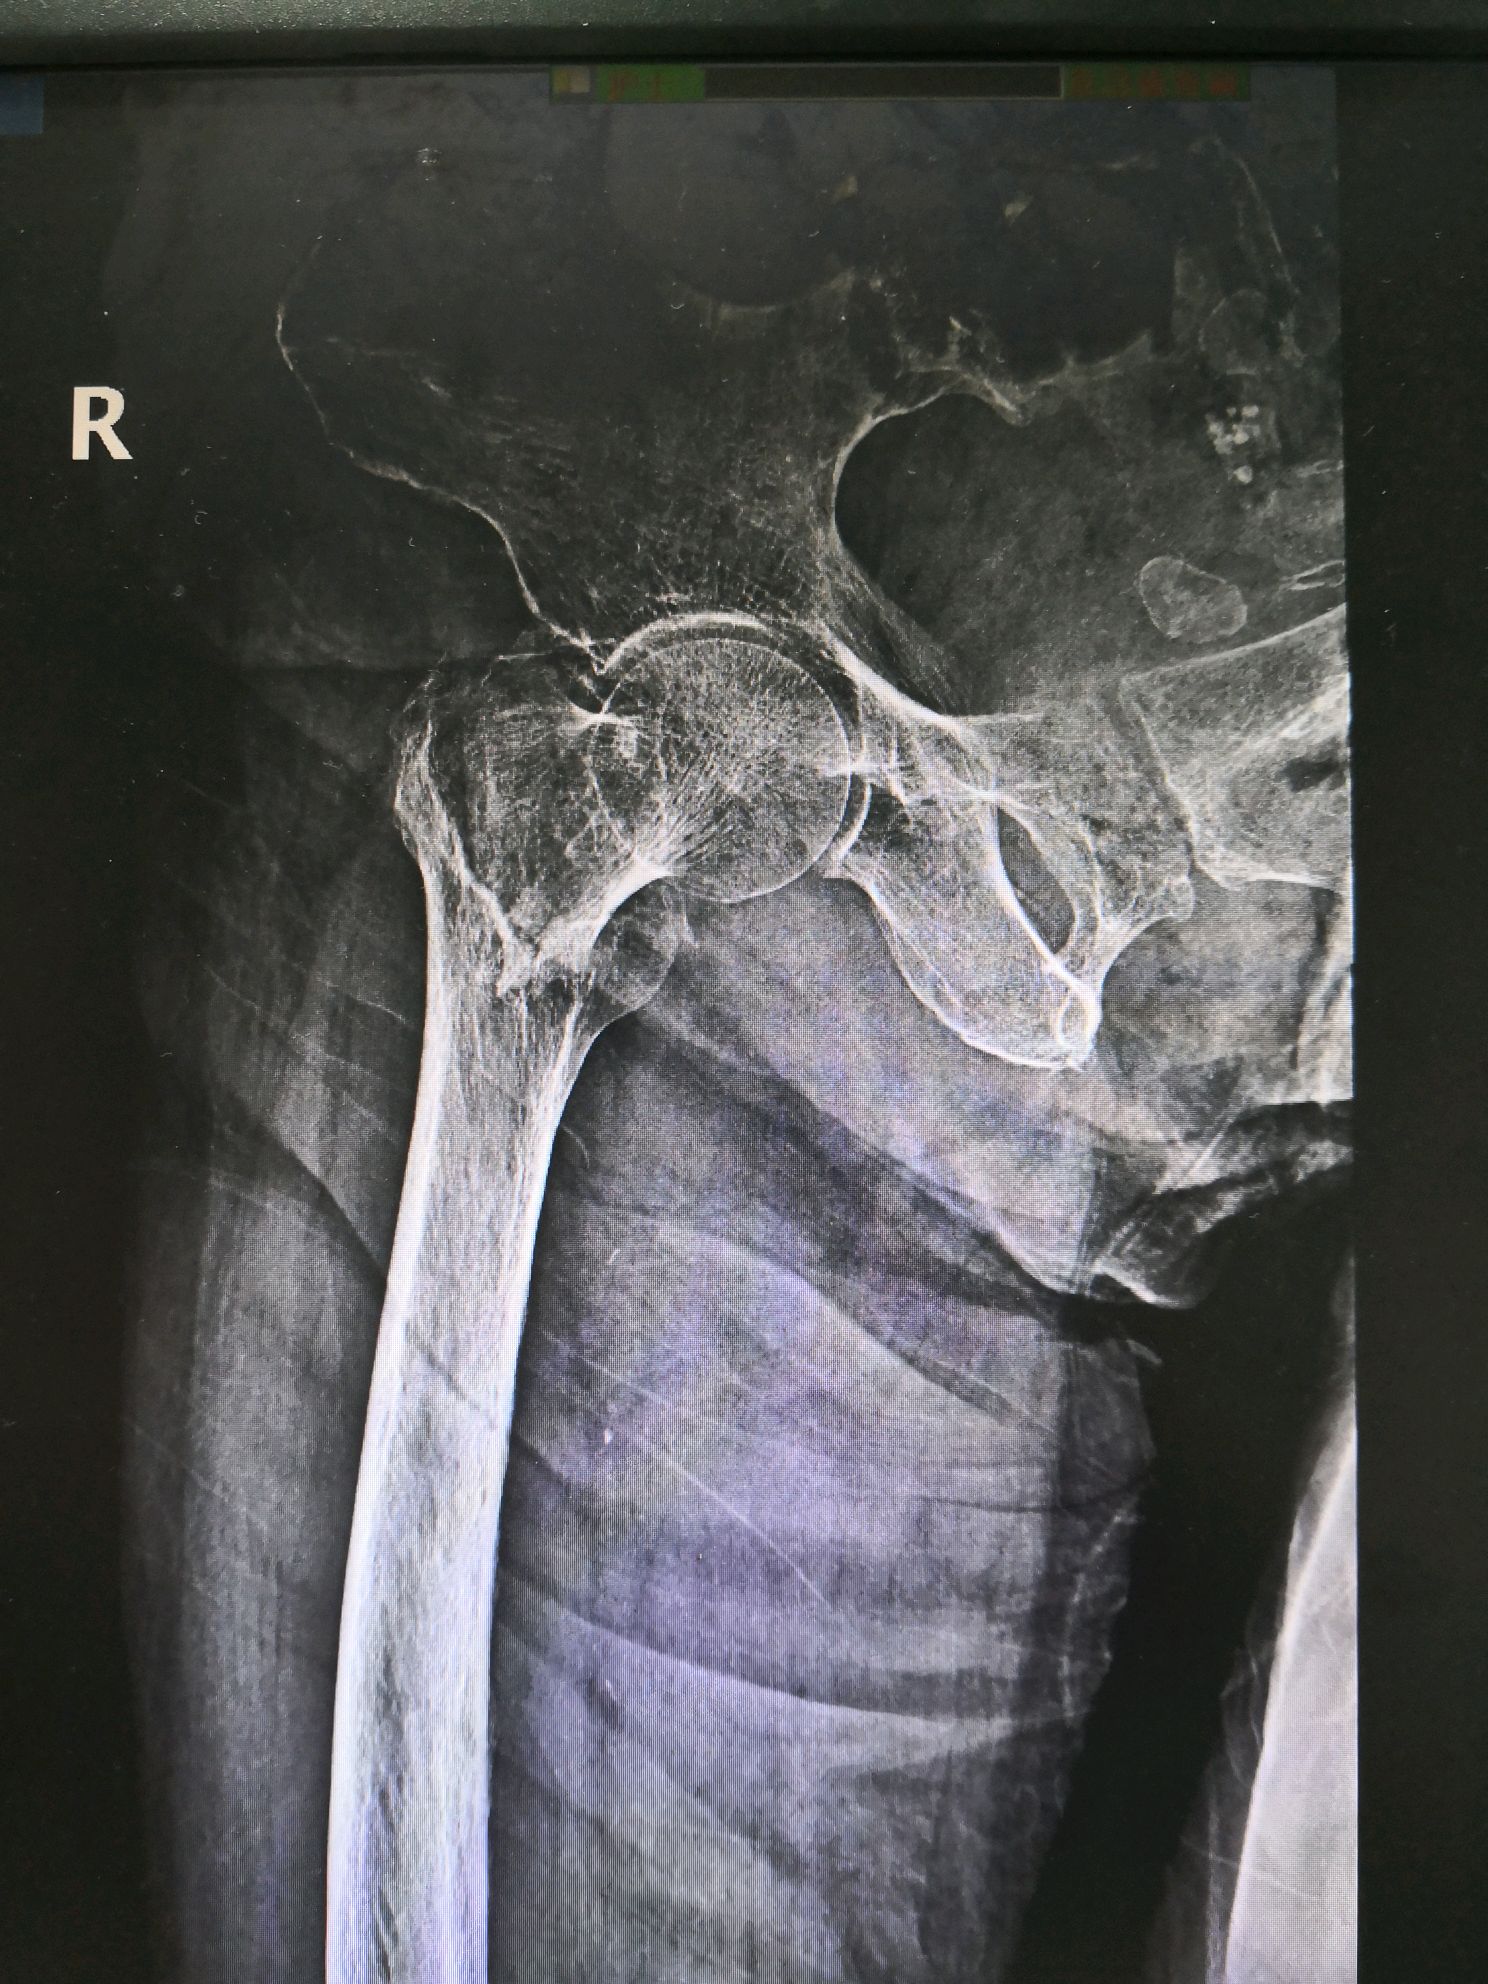

图片经患者同意才上传。下面我把几个患者的术前骨折片及术中、术后X光片传上来让大家有个认识。

很幸运,5例手术效果都很好。总结一下:股骨转子间骨折是老年髋部骨折最常见的类型,特别是骨质疏松的老年女性,下雨天不要让老人出门,厨房、洗水间要装防滑的软垫,老人房间没洗水间的,要准备尿不湿,很多老人夜尿多,半夜起床上洗水间不敢开灯,怕影响到别人。髋部受伤后要及时就医,拍X光片,确定股骨转子间骨折后不要认为合并有很多慢性病就拒绝手术,能不能手术由医生做完检查后评估,这类手术是能微创做的,使用lNTERTAN髓内钉技术,能让骨折恢复力线,没有疼痛,早期能坐轮椅外出和下床行走,提高生命质量,享受更快乐的晚年。感谢5位并肩作战和支持我的老人家,你们的笑容很灿烂,我会永远记得的!